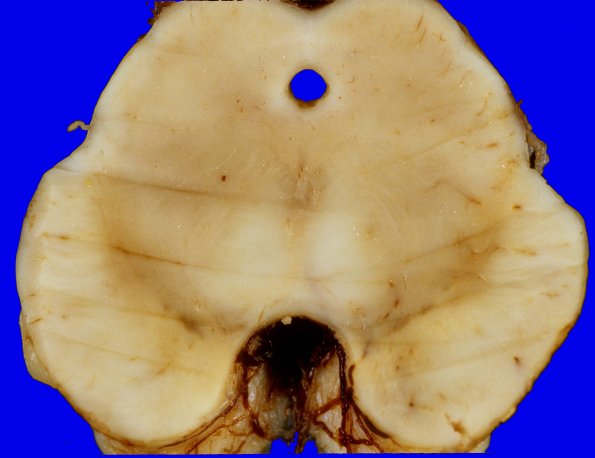

The midbrain sections show loss of pigmentation in the lateral aspect of the substantia nigra.